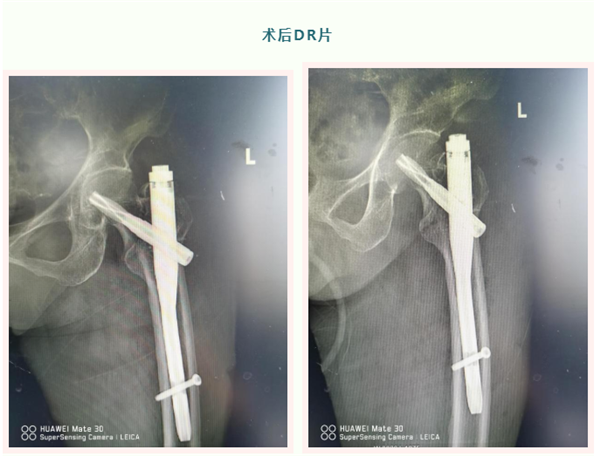

我院常规采用闭合复位PFNA内固定术,手术创伤小,结合中医辨证施治,调理气血。术后恢复快,大多数患者都能走着出院,大大减轻了患者的痛苦,减少了家庭及社会负担。

骨伤科一位老奶奶今年84岁,在家看鸭子时不慎摔伤,致左髋部骨折。